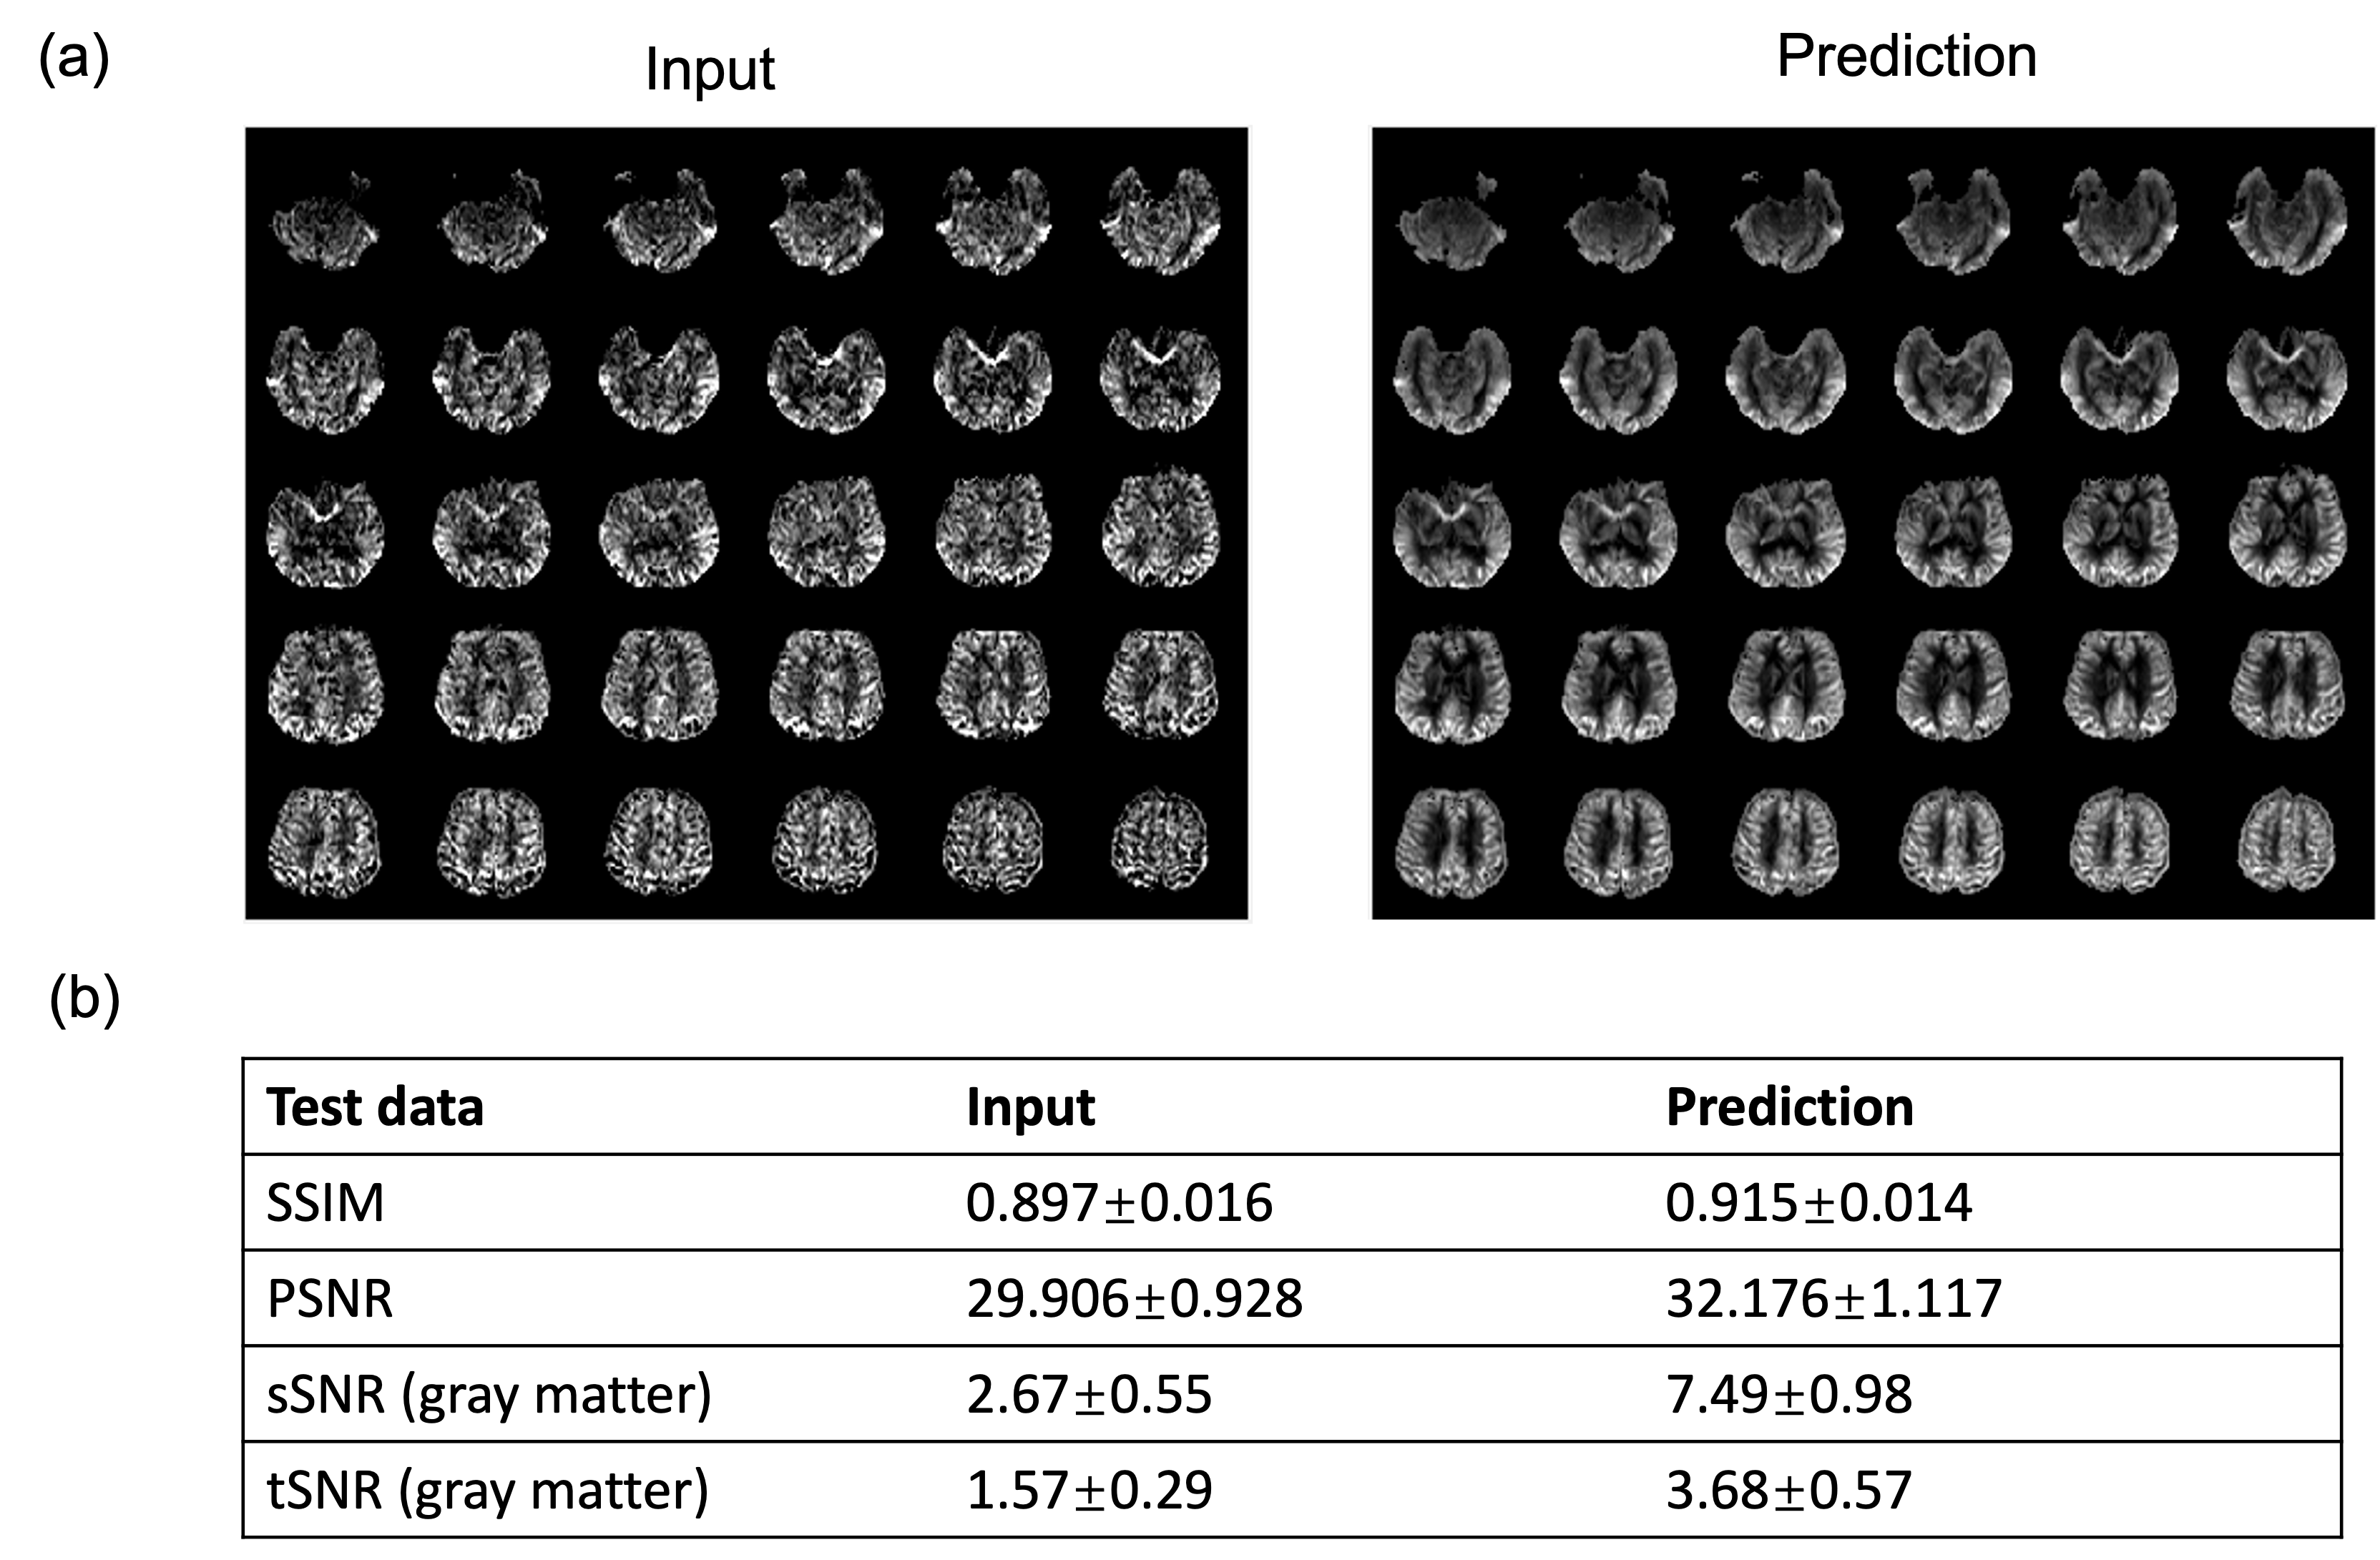

Figure 2 shows the results for the first test dataset, the image for the DL prediction has improved SNR compared to the input. The similarities metrics are also consistent with the visual quality, SSIM and PSNR after DL denoising were improved by 2% and 7.6%, while spatial and temporal SNR were improved by 181% and 134% respectively. Figure 3 shows the results for the second dataset, SSIM and PSNR were improved by 1.4% and 3.9%, while spatial and temporal SNR were improved by 71% and 42% respectively. Figure 4 shows the results for the multi-delay dataset. DL prediction has improved the SNR for perfusion images at each PLD, and improved SNR for the fitted CBF and ATT maps. Figure 5a shows that the global CBF values calculated from the DL prediction is highly consistent with those from the single-delay input images. Figure 5b and 5c show that the fitted CBF and ATT values from the DL predicted multi-delay perfusion images are also consistent with those fitted from the input images.

Figure 3. The input and prediction on the second test dataset (A different cohort from the training data). (a) Input perfusion image and the DL denoised perfusion image of one subject. The DL denoised image has higher SNR compared to the image. (b) The quantitative results of the input and DL-predicted image. DL denoised image has higher SSIM and PSNR compared to the input image, as well as higher spatial and temporal SNR.